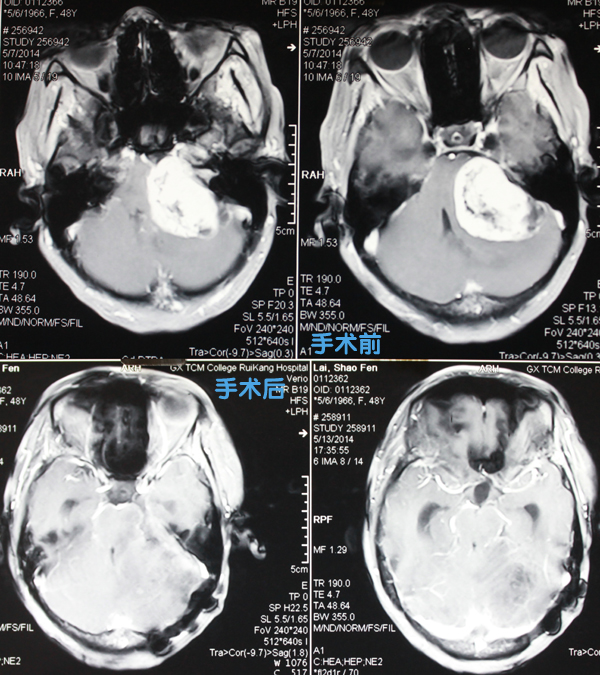

术前术后对比

48岁的赖女士头痛头晕两个多月了,慢慢地她的嘴角变得歪斜,在五月初还出现了行走不稳的症状,她不知道在她左脑内一颗肿瘤正在膨大,已经影响到正常的身体功能了。

术中,医生发现,病人肿瘤位于左侧桥脑及小脑角处,约鸡蛋大小,三叉神经被挤向前方,脑桥受压变扁,面神经及后组颅神经更是被肿瘤挤压得“面目全非”,分散于肿瘤表面,让人辩认困难。医生们只能在显微镜下逐一剥离,从细小的神经间隙中小心翼翼地将肿瘤体中心部分掏出,再将瘤体包膜与神经精细分离,即保全了三叉神经、面及后组神经的完整,又全切了肿瘤,这一剥离过程就耗去了9小时。在医生们的严密监控和操作下,手术后患者没有出现肺部和颅内感染,手术完成得非常漂亮。

据医院神经外科主任范学政介绍,肿瘤大小比正常生命中枢脑干还大,肿瘤对脑组织周围压迫比较严重,颅压很高。另外,肿瘤紧贴人体生命中枢、运动中枢,术后有可能会危及到患者生命、肢体的活动,而肿瘤本身供血非常丰富,手术的过程中出血会比较多。